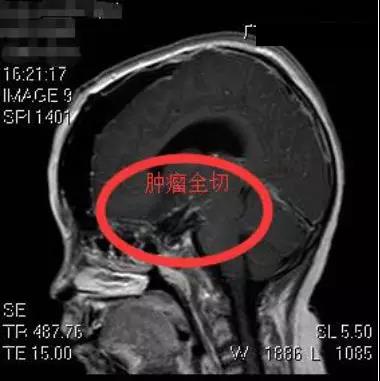

近日,广东三九脑科医院副院长、神经外五科主任鲁明成功将小明颅内的巨大颅咽管瘤切除。

5月22日,鲁明为小明在全麻下行巨大颅咽管瘤切除术。术中发现肿瘤巨大,包裹了颈内动脉、大脑前动脉和中动脉,且肿瘤位于脑深部,钙化明显,质地坚韧,手术难度极大。经过手术团队近12个小时的奋战,才终于顺利将肿瘤切除。术后测量显示该颅咽管瘤大小约5cm×5.6cm×7.7cm厘米,比鸡蛋还大。目前小明恢复良好。